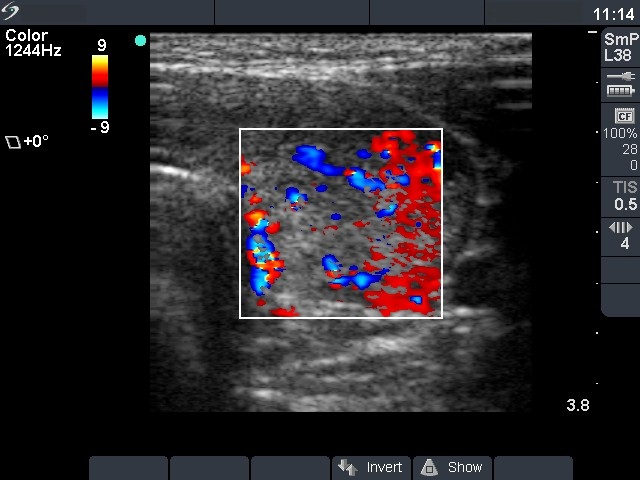

Left lobe, transverse scan, color Doppler mode. The vascularization is increased.